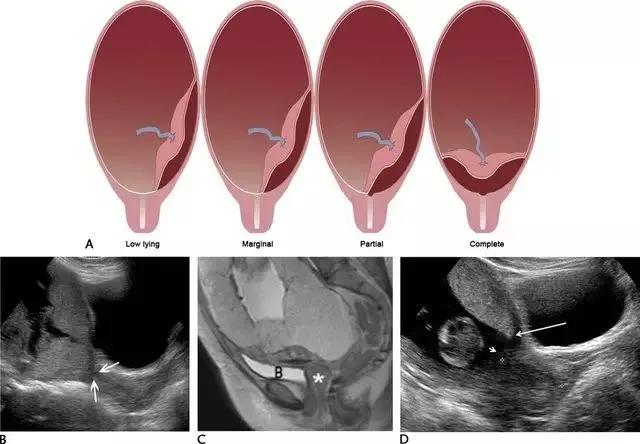

胎盘附着异常:包括胎盘粘连、胎盘植入及胎盘穿透(图 11)。胎盘粘连指胎盘组织向子宫肌壁延伸,但并未对其构成实质性的侵袭,占所有胎盘附着异常的75%。

胎盘植入指胎盘组织已侵入子宫肌壁,但并未突破浆膜层。穿透指不仅侵入肌壁,且已突破至浆膜层之外,可导致子宫的毗邻器官如膀胱、肠管及腹壁受累。超声是本病的主要显像方法,在临床高度怀疑本病或超声检查为阴性或不确定时,可使用 MRI(图 12 和图 13)。

图 11 为胎盘附着示意图 ,自最左图向右分别为正常、粘连、植入、穿透

图 12 示胎盘粘连:A 为孕 32 周患完全性前置胎盘(此图未显示)孕妇的子宫前壁横切面(线阵探头所得),可见肌壁由上至下、向膀胱子宫陷凹方向逐渐缺乏、变薄(短箭头所示)。B 为另一孕妇的冠状位 MRI,孕期经常性左腹痛,超声考虑胎盘粘连,长箭头示胎盘下方的低信号肌壁由左向右逐渐变薄。此 2 例均在剖腹产时被证实为胎盘粘连

图 13 示合并有完全性前置胎盘的胎盘穿透,患者有 2 次剖宫产病史:A 为子宫纵切面,箭头示肌壁逐渐变薄、子宫与膀胱之间的界限模糊,胎盘下的闲置空间消失(B :膀胱)。B 为同一患者的子宫矢状面,箭头示大量不规则紊乱血流向肌壁延伸。图 C 为另一孕妇 28 周时的矢状位 MRI,可见前次剖腹产瘢痕上缘存在胎盘对子宫前壁的侵犯、肌壁连续性局部中断(箭头)